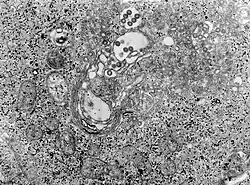

TEM micrograph of tissue infected with Rift Valley fever virus | |